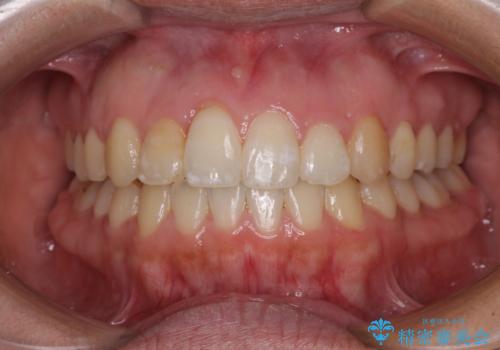

治療開始後すぐに妊娠され、つわりと闘いながらの矯正治療となりました。

上下顎でゴムかけを行ったのですが、早く終わらすためにしっかりと装着していただき、無事出産前に装置を外すことができました。